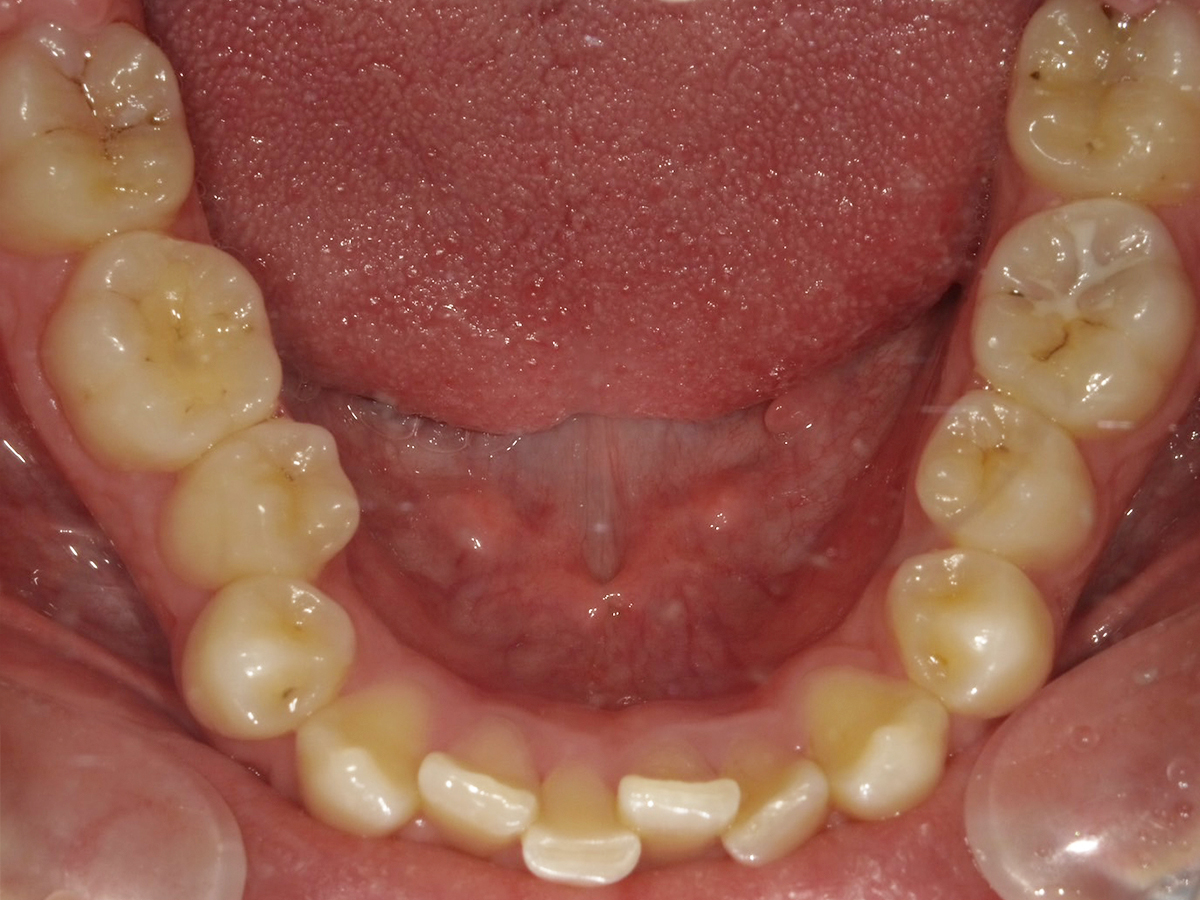

No.001|Bさん(男性)

インビザライン

- インビザライン

- 20代

- 約30ヶ月